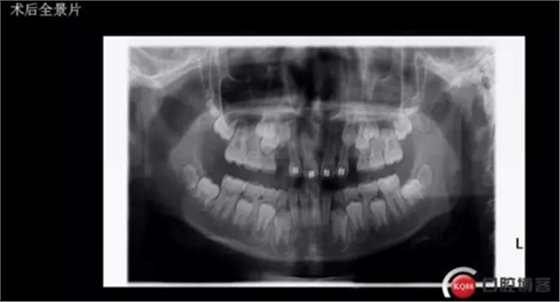

拔掉一顆后大概大半年時(shí)間很快就把間隙關(guān)閉了,但是由于還有一顆橫在兩中切牙間,牙縫始終得不到完全關(guān)閉,此時(shí)只能拔掉深部埋伏阻生的牙才能進(jìn)一步矯正治療,但小孩一聽(tīng)又要做一次手術(shù)有不同意了,這樣又拖了兩年多,長(zhǎng)大了一些自然懂事了些。

確定了方案和術(shù)前良好溝通和小孩良好的配合,牙齒很快就拔了出來(lái)。

年輕就是優(yōu)勢(shì),牙齦長(zhǎng)得非常快非常好!

術(shù)后思考:患兒如今已經(jīng)十一歲多, 雖然已經(jīng)給尖牙騰出了位置,然而全景片顯示兩顆尖牙位置依然很深,是主動(dòng)出擊還是靜觀其變呢?歡迎大家共同探討!